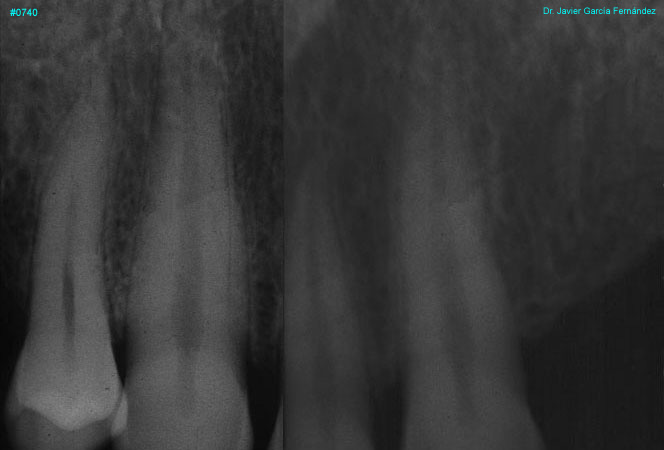

Atlas of Surgical Techniques in Periodontics. Chapter III. Atlas de Técnicas Quirúrgicas en Periodoncia